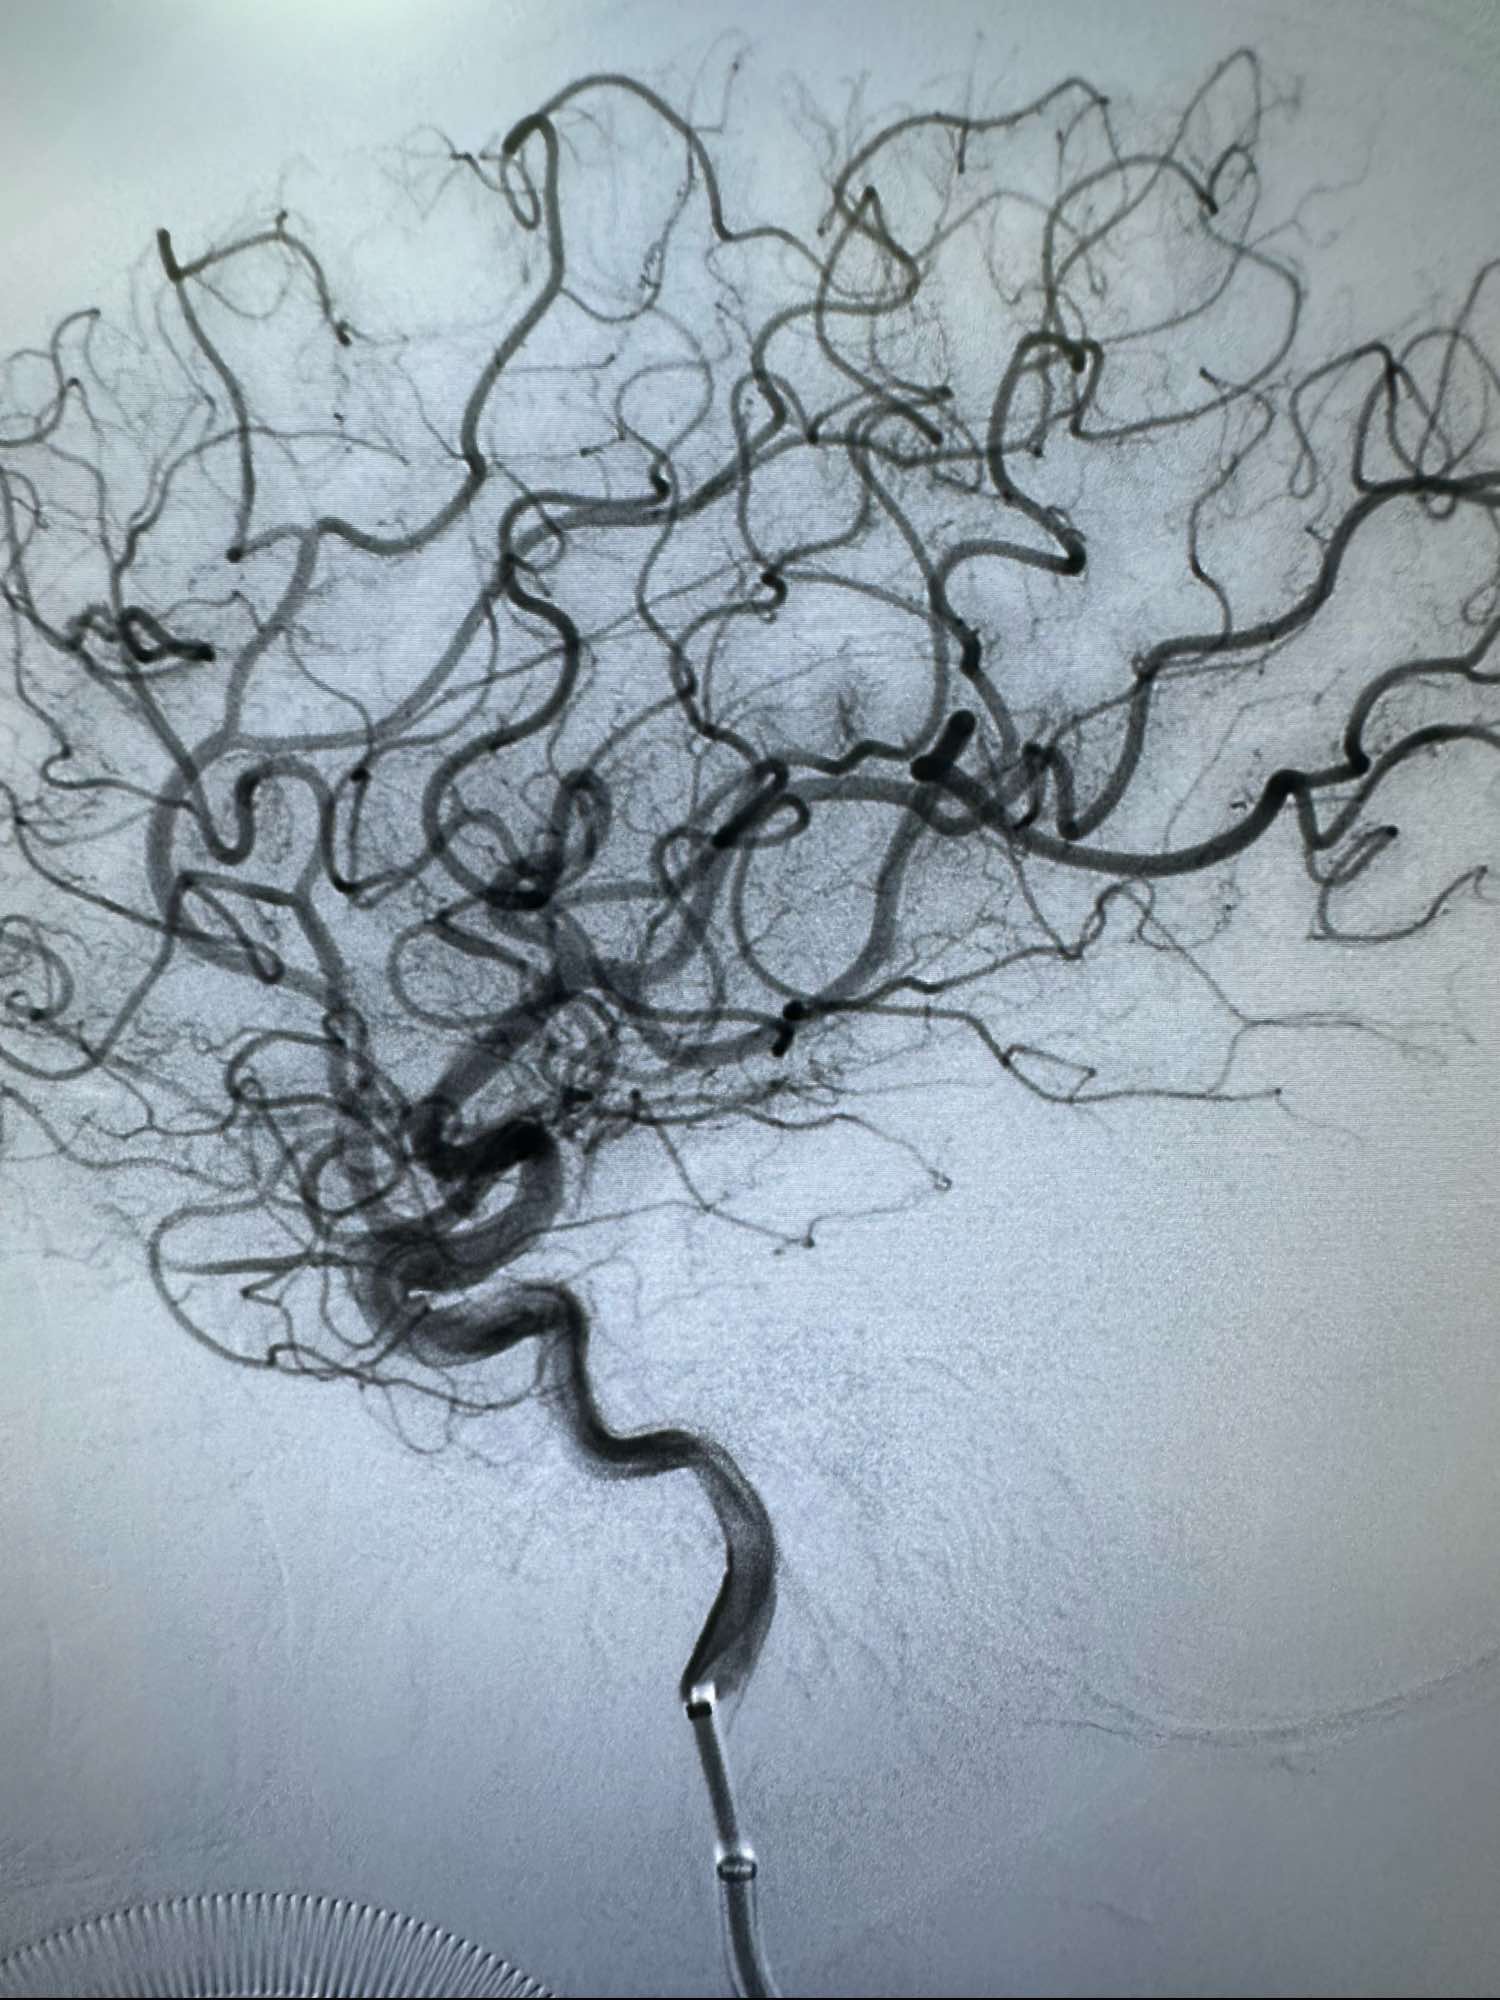

左侧颈内动脉造影正位